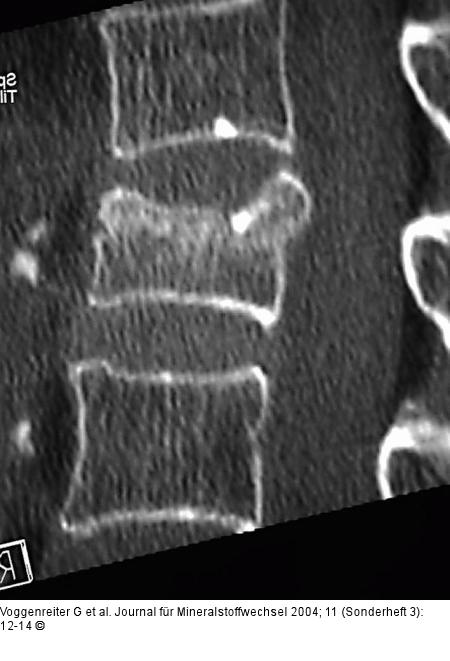

Abbildung 2a-c: LWK1-Fraktur 67jährige Patienten mit einer 4 Wochen alten LWK1-Fraktur und ausgeprägter Schmerzsymptomatik. In der TIRM-Sequenz des MRT erkennt man eine deutliche Signalanhebung in LWK1. |

Abbildung 2a-c: LWK1-Fraktur

67jährige Patienten mit einer 4 Wochen alten LWK1-Fraktur und ausgeprägter Schmerzsymptomatik. In der TIRM-Sequenz des MRT erkennt man eine deutliche Signalanhebung in LWK1. |